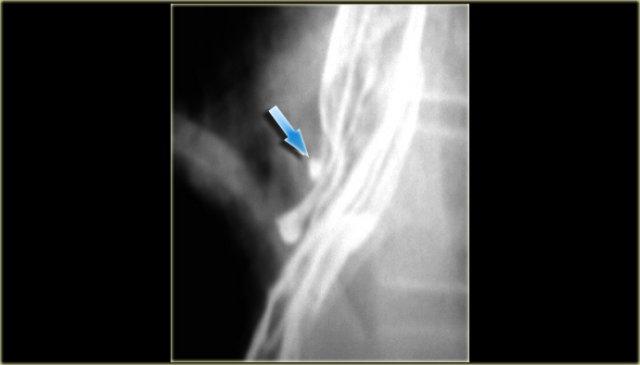

Phim chụp thực quản cản quang cho thấy các khuyết đọng thuốc không hằng định (mũi tên xanh dương) do giãn tĩnh mạch hướng xuống ở thực quản trên.

CT cho thấy giãn tĩnh mạch thực quản (mũi tên đỏ) và trung thất.

Tiếp tục xem hình chụp tĩnh mạch.

Hình chụp tĩnh mạch chi trên cho thấy tắc nghẽn tĩnh mạch chủ trên (SVC).